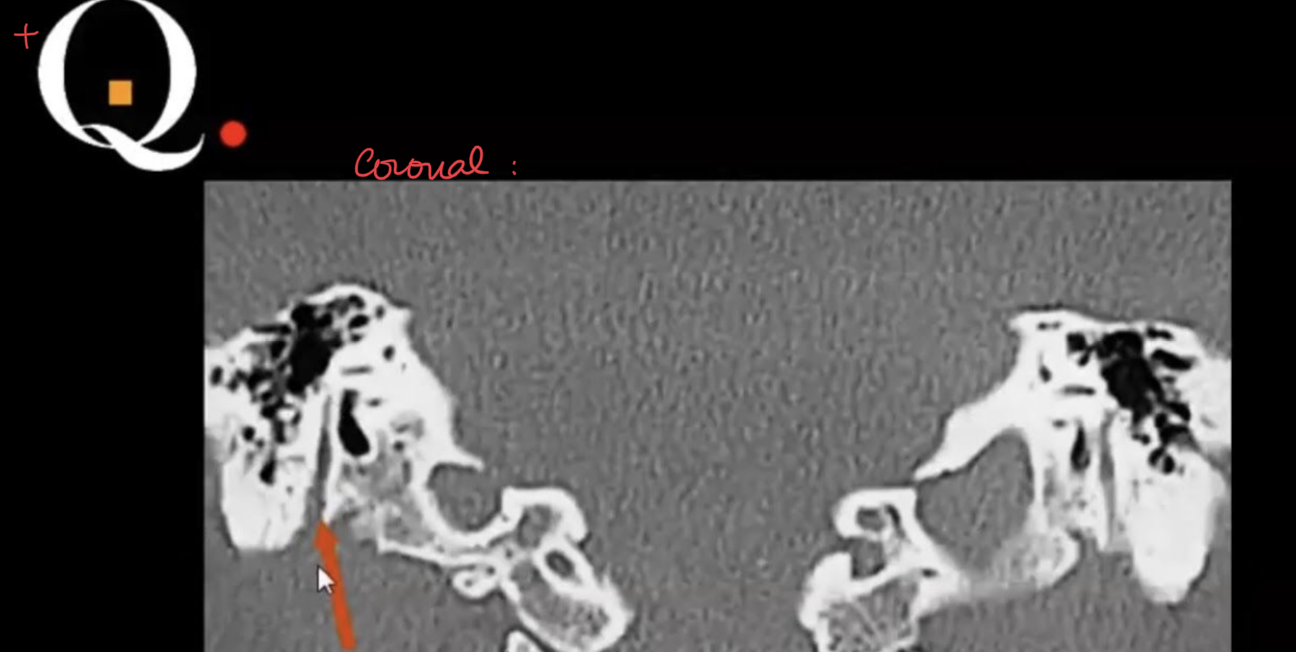

Tell the traject of the facial nerve in the skull base?